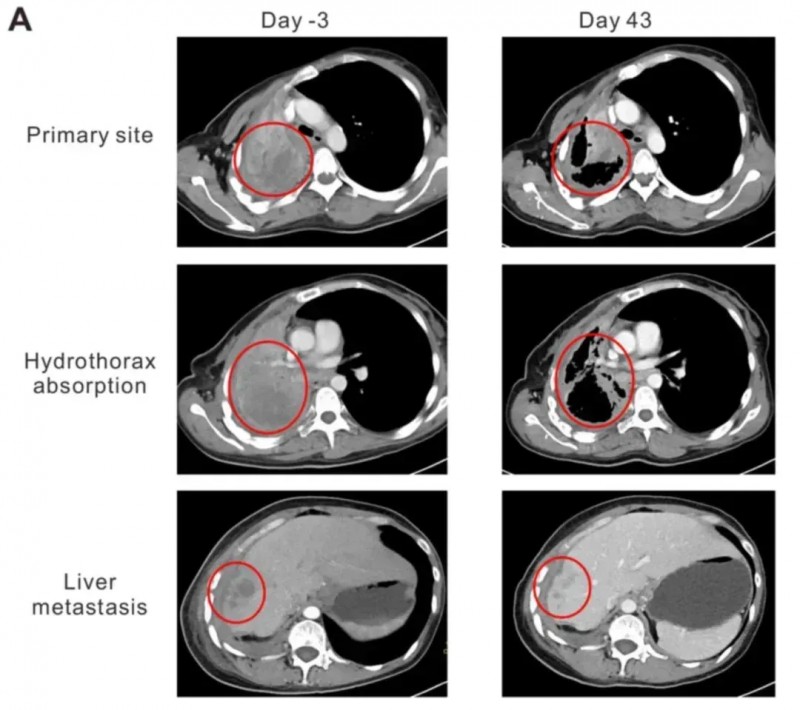

值得一提的是,其中一例晚期肺腺癌女性(患者2),在接受治疗后不仅达到部分缓解(PR),且无明显毒性,生活质量与临床症状显著改善:卡氏功能状态评分(KPS)从50分提升至90分,咯血、胸痛症状明显减轻,胸腔积液完全吸收、肺组织复张。同时,其血清中细胞因子IFN-γ水平在细胞输注后第二周达峰值(首次输注后48.92pg/ml,二次输注后47.63pg/ml),随后逐渐回落。更直观的是肿瘤缩小数据:治疗第43天的CT显示,肺部原发灶从95×86×54mm缩小至64×44×54mm,肝部转移灶从19.8×19.6×20mm缩减至10×10×10mm。

▲图源“OncologyLetters”,版权归原作者所有,如无意中侵犯了知识产权,请联系我们删除